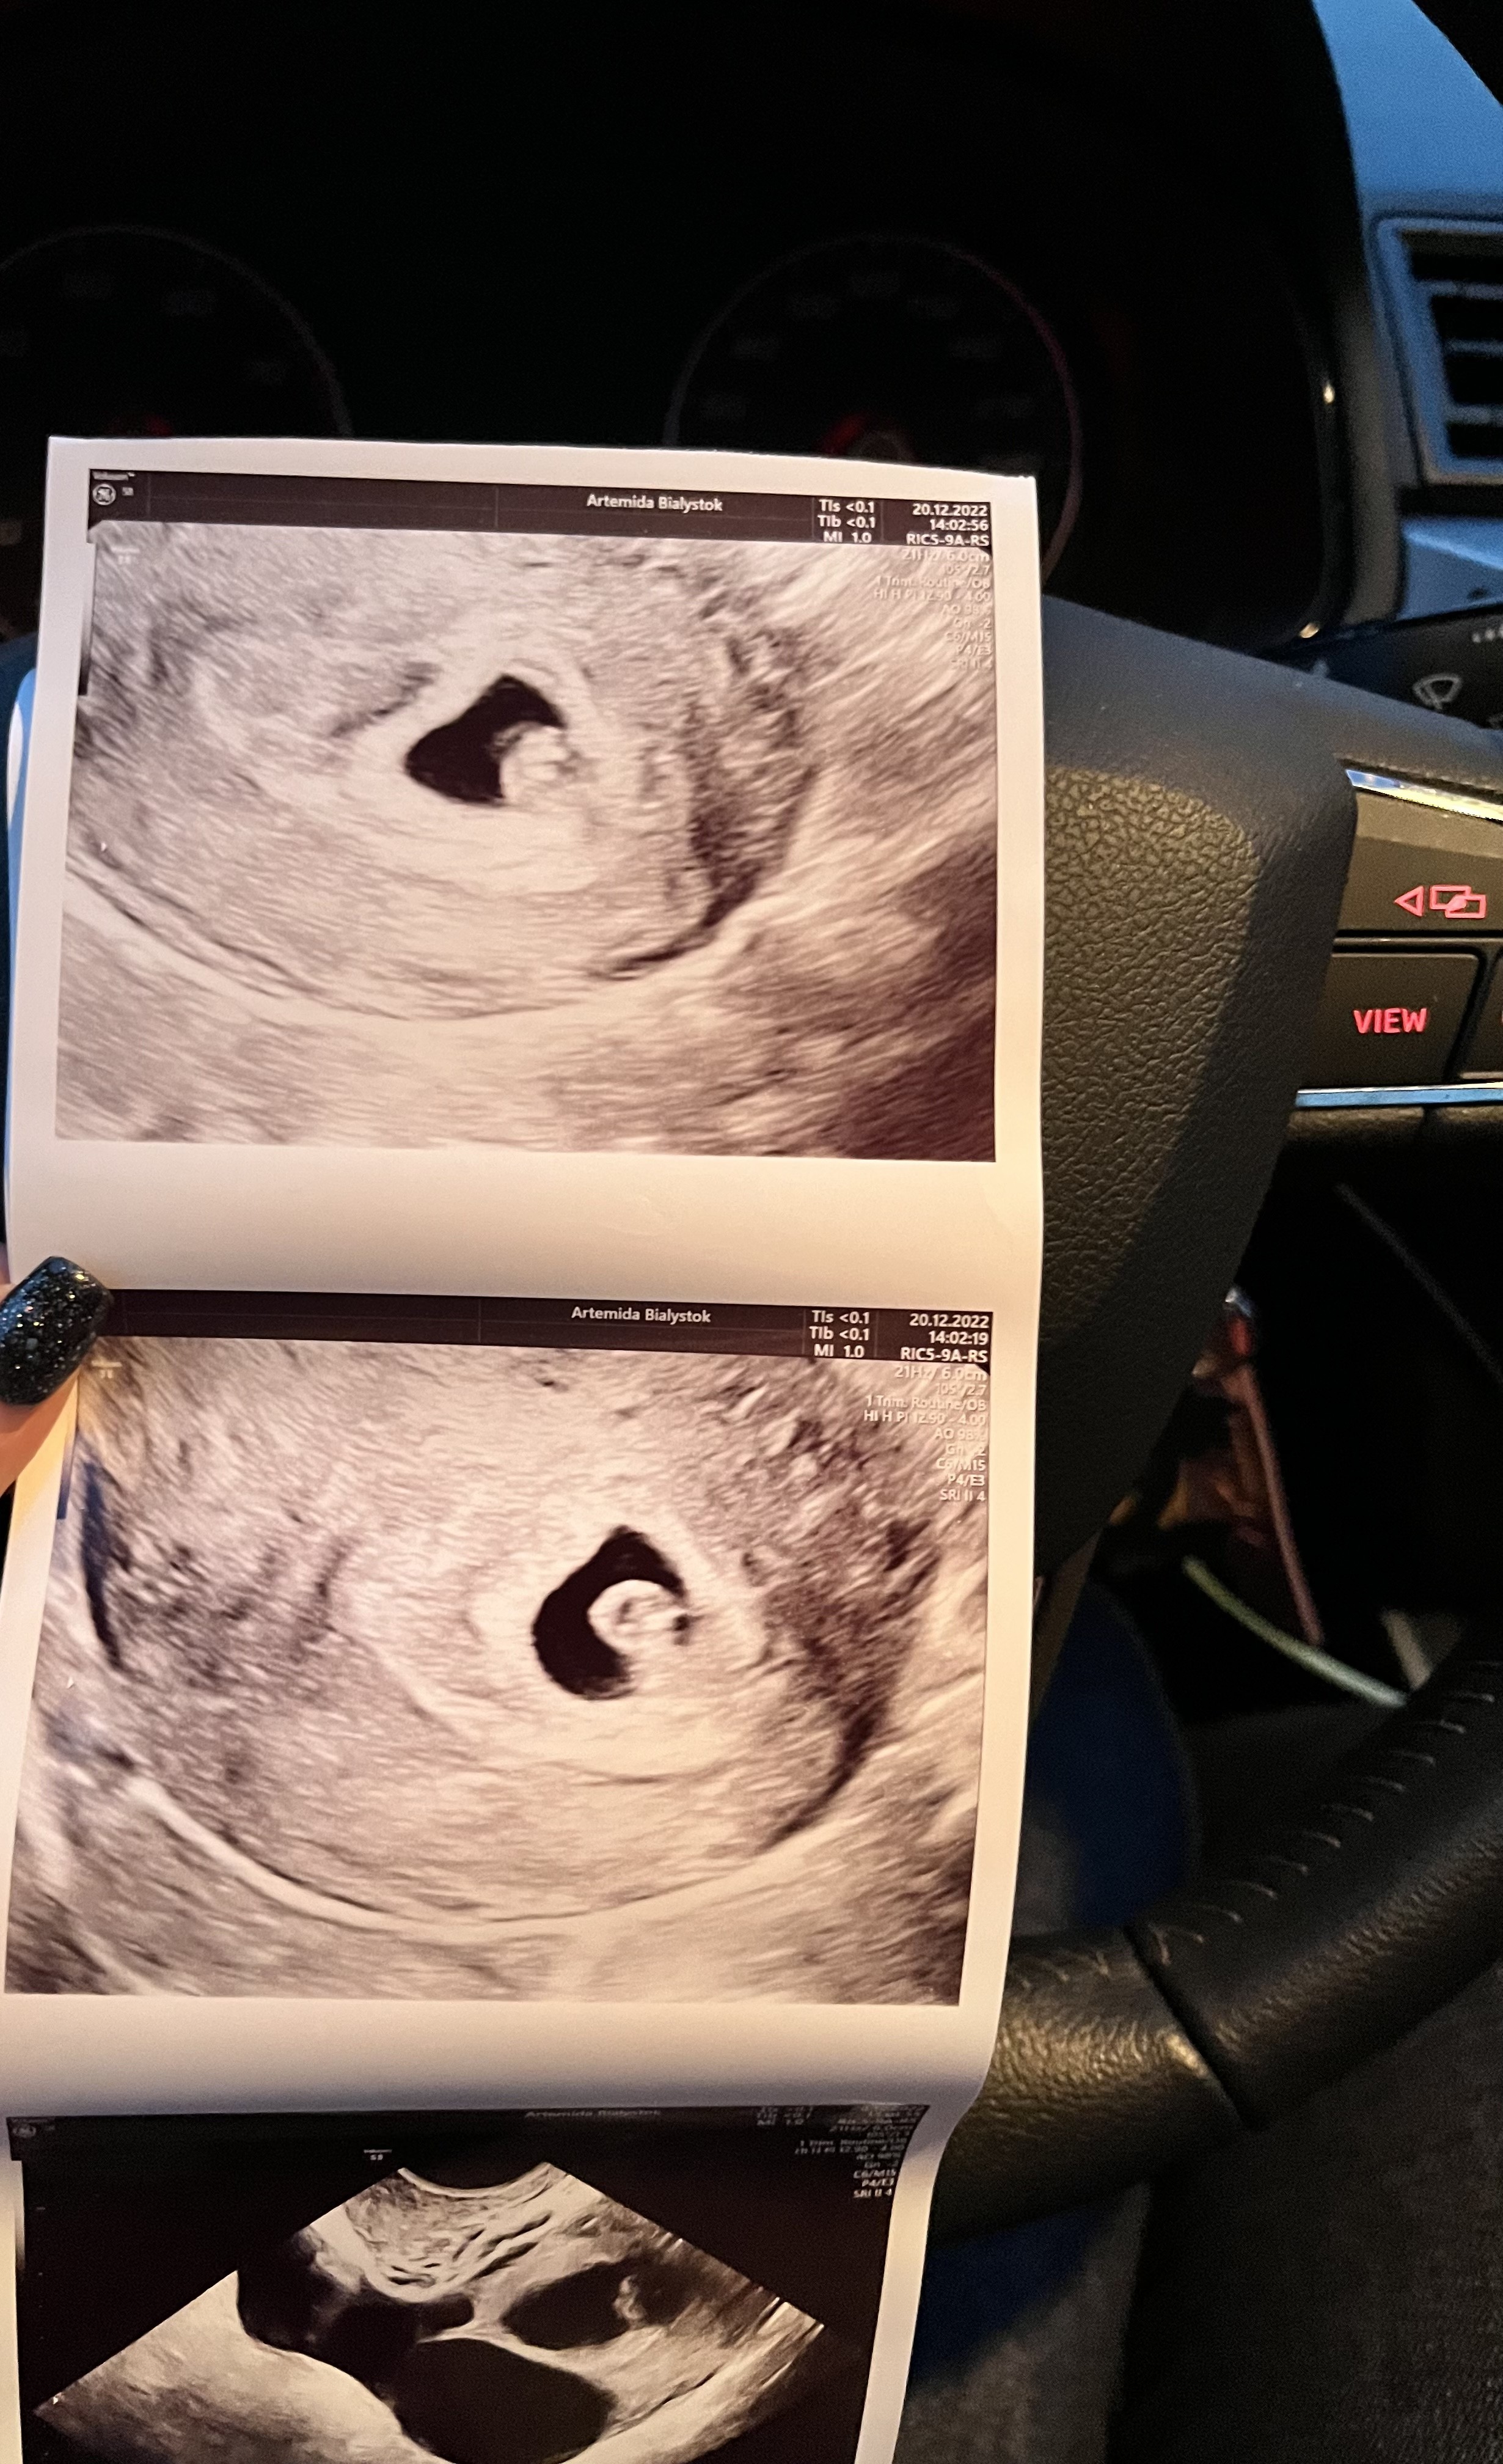

Już jestem po. Wiedziałam, że jeszcze nie będzie widać serduszka, tym bardziej że po pomiarach stwierdził że młodsza niż 5 tyg. Ake to akurat niemożliwe. Mój mąż jest tylko na weekend. Wiem, kiedy musiało dojść do zapłodnienia. Tym bardziej że testy owu były pozytywne. W każdym razie na razie cieszę się z kropki - a raczej kropek 😁😁😁 bo pęcherzyki są dwa! Oby się wszystko udało i się utrzymały. Byłabym przeszczesliwa z bliźniąt! Tak zapisał "ciąża mnoga, dwuowodniowa, dwukosmowkowa" 🙂

Ja też już jestem po :) u mnie 6 tydzień i widziałam już serduszko 😍 też mam już kartę ciąży